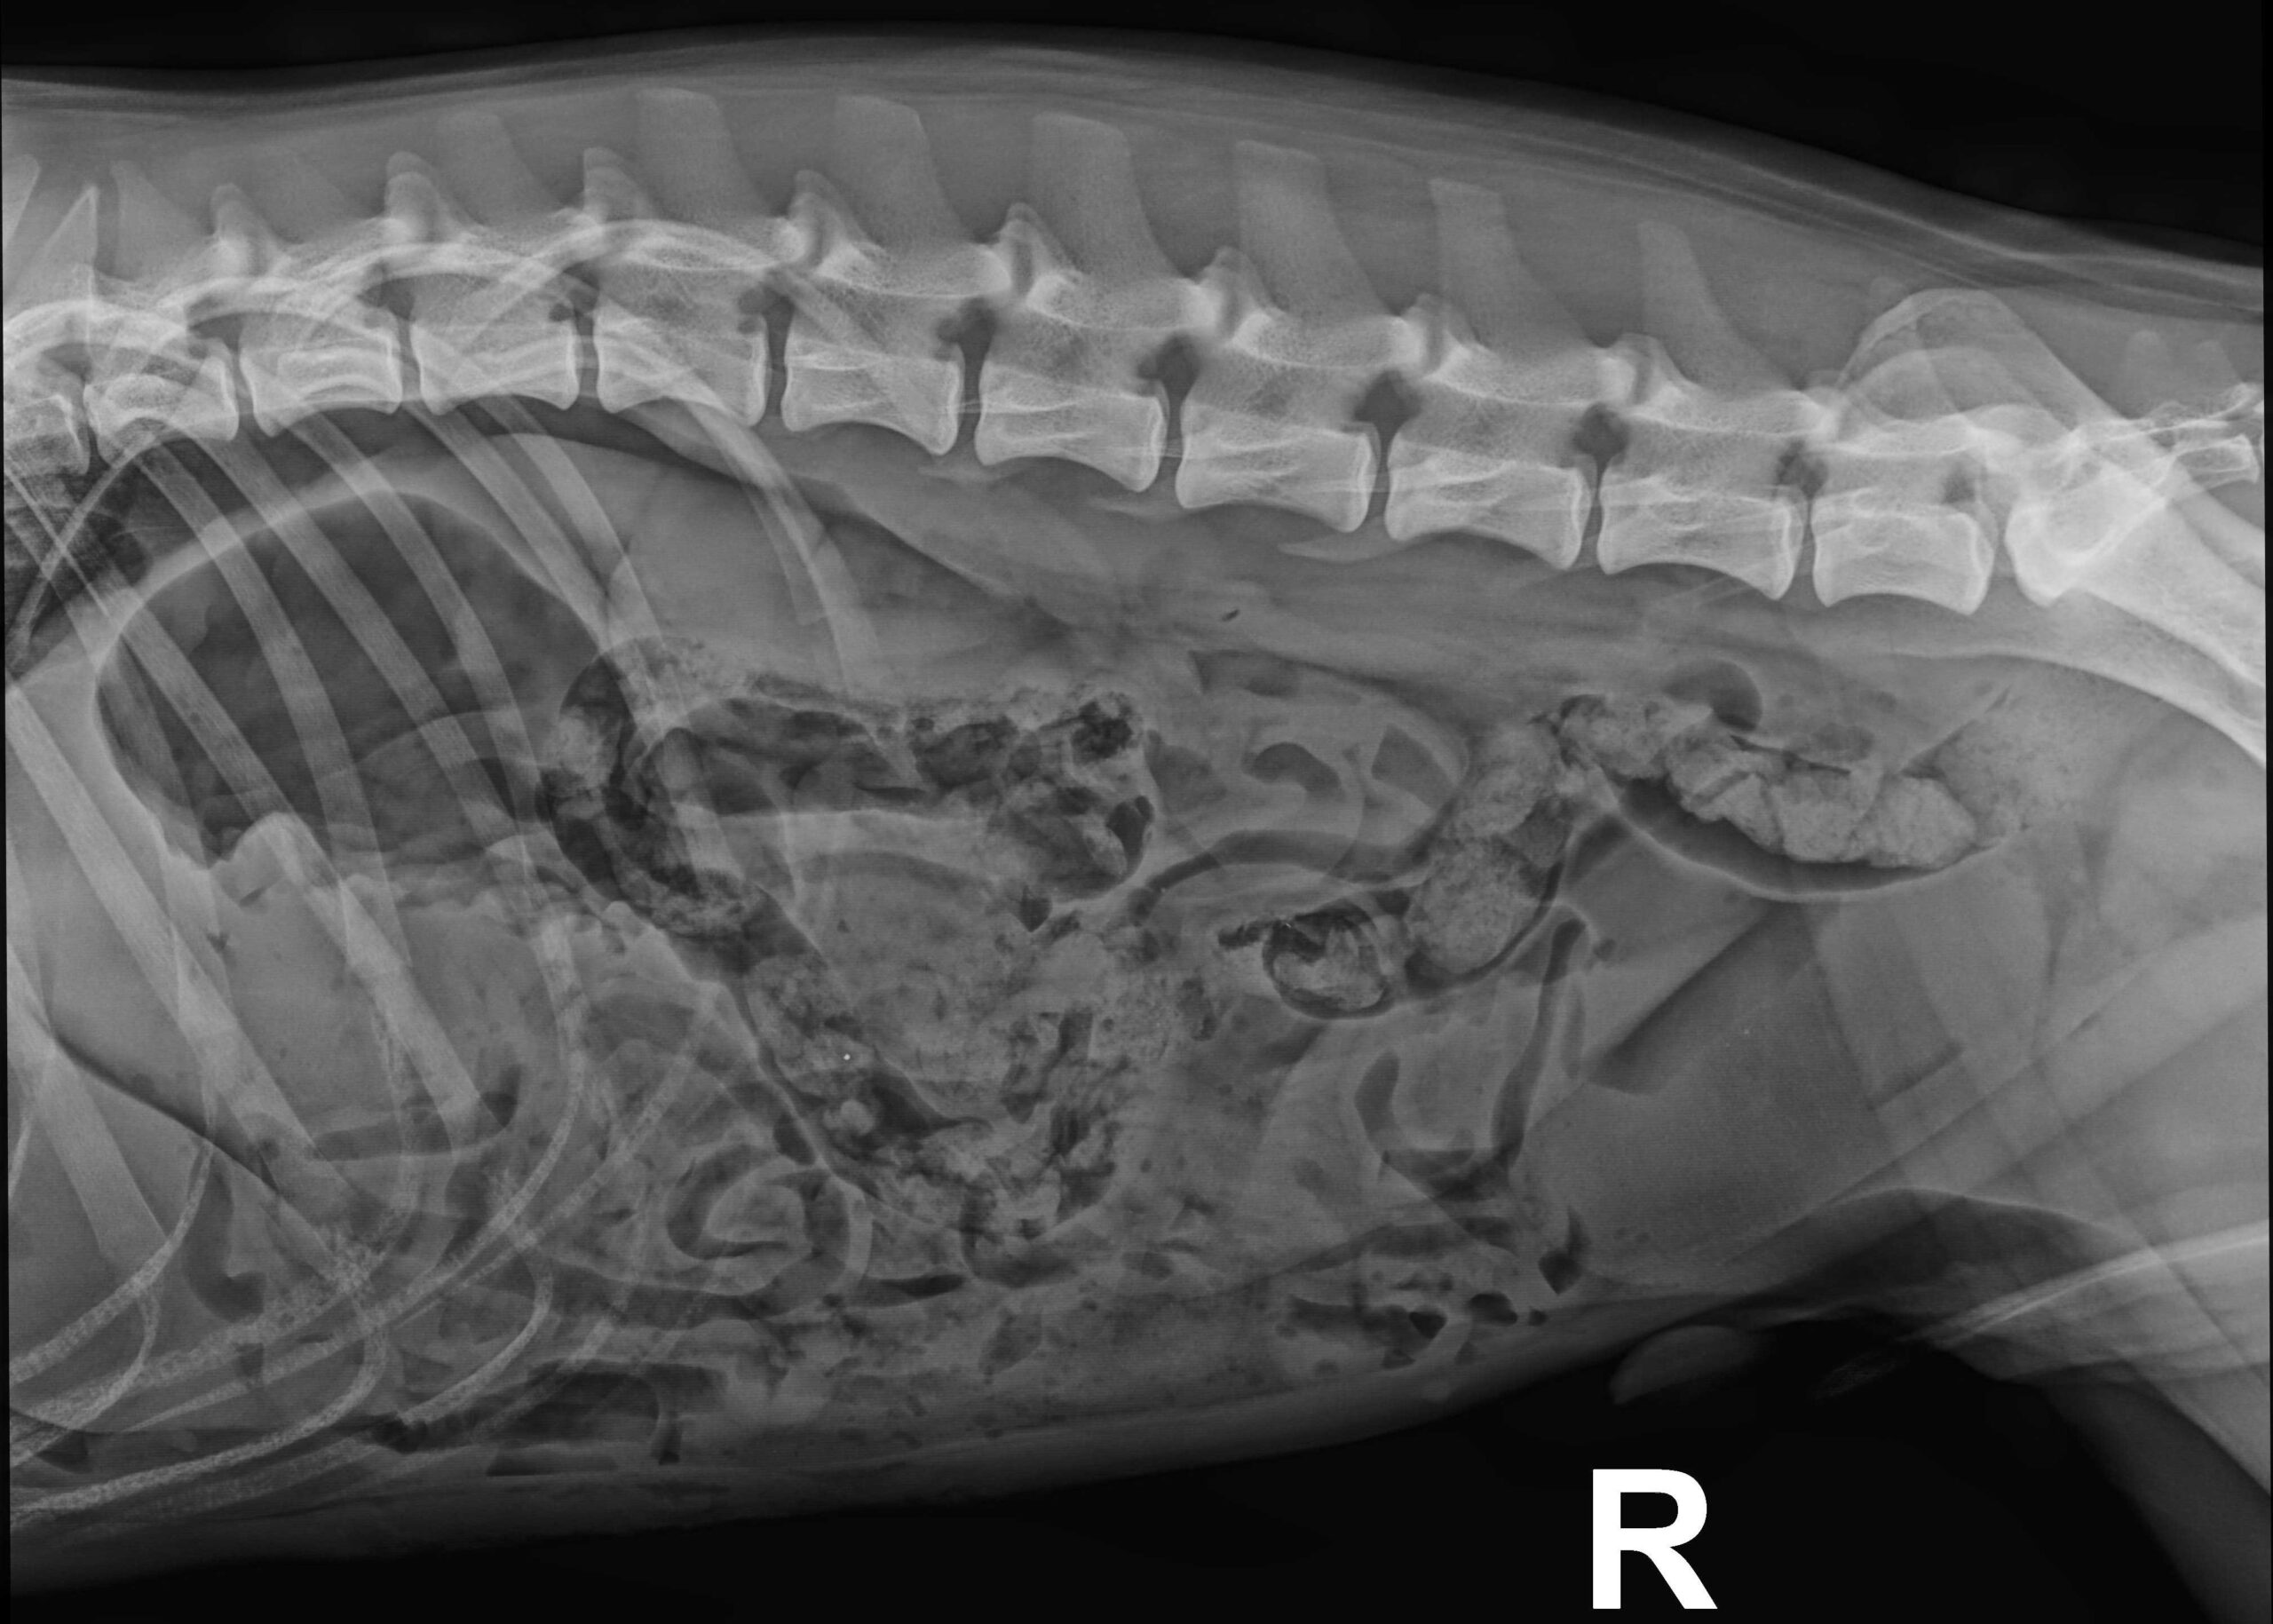

So konnte der Stein entfernt werden, eben ohne den Magen aufschneiden zu müssen. Diese Vorgehensweise ersparte Rio eine belastendere OP und verkürzte die Erholungszeit erheblich. Bereits am Abend durfte der Hund wieder mit nach Hause.

Röntgenbild nach der OP: Der Stein konnte ohne Magenschnitt entfernt werden.